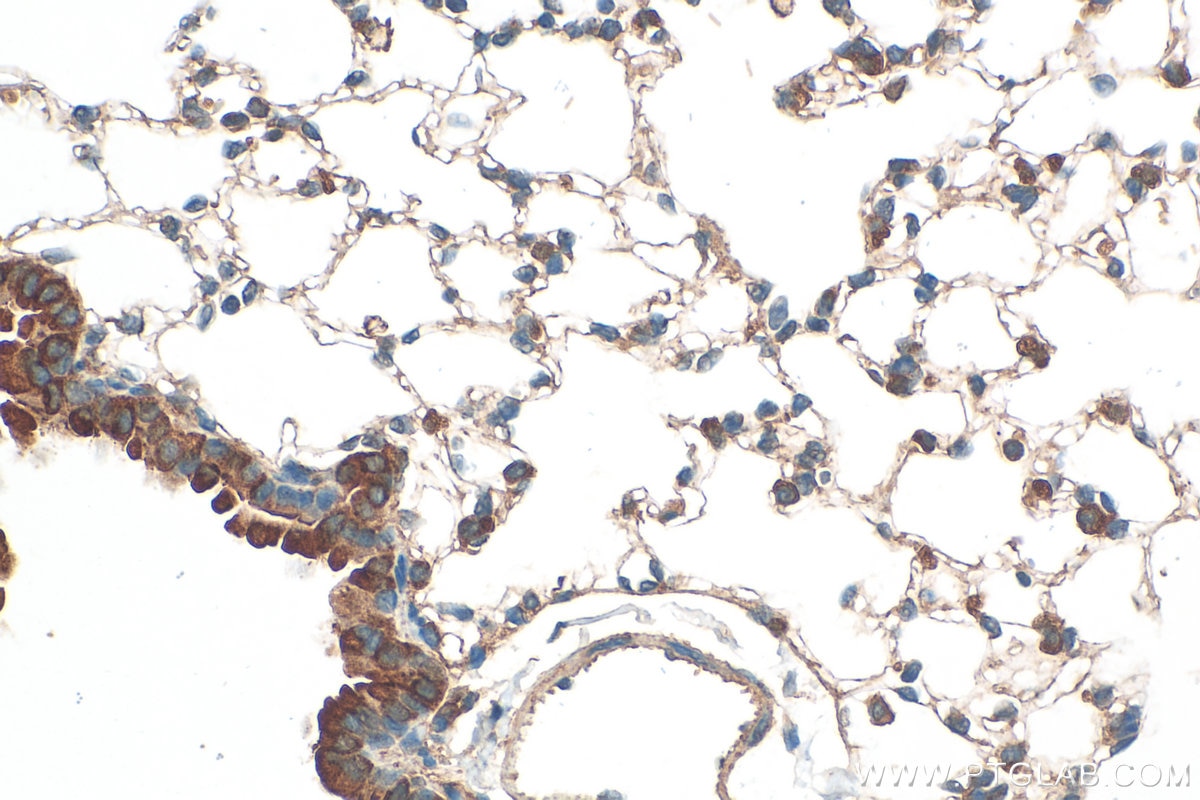

| Positive IHC detected in | human intrahepatic cholangiocarcinoma tissue, mouse lung tissue Note: suggested antigen retrieval with TE buffer pH 9.0; (*) Alternatively, antigen retrieval may be performed with citrate buffer pH 6.0 |

| Immunohistochemistry (IHC) | IHC : 1:50-1:500 |